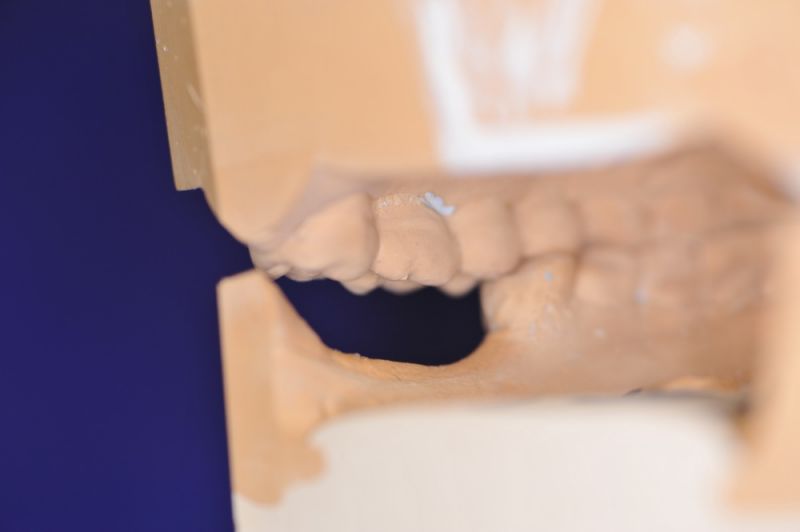

Es war eine Kombination aus Schmerzen bis an die Suizidgrenze, beschränkten wirtschaftlichen Möglichkeiten, sehr stark eingeschränkten Möglichkeiten der für Implantate zur Verfügung stehenden Knochenverhältnisse in einem stark atrophierten Unterkieferseitenzahnbereich und zudem dann auch noch durch auftretenden Problemen bei der Implantatinsertion und nachfolgenden Versorgung der Implantate.

Die Problematik der Implantatversorgungen kann man in einer Analogie folgendermaßen darstellen. Die räumlich beengten Zustände gleichen dem Tanz eines Paares auf einer Briefmarke, und der gleichzeitigen Schritt- und Fusshaltung, dass beim Tanzen die Schuhe geputzt werden können!